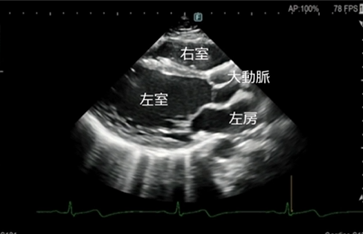

当院では、短時間・低負担での撮影が可能なCTや、放射線を使用しないオープンMRIを利用し、必要に応じて隣接医療機関の高度な検査機器も共同で使用しています。 - 超音波検査(エコー)

お腹の臓器、心臓、血管などを、体に負担をかけずにリアルタイムで観察します。

しこりや腫瘍、血流の状態なども調べることができます。 - 血圧脈波検査(CAVI検査)

心エコー検査は、超音波を用いて心臓の形や動き、血流の流れを詳しく観察する検査です。

放射線を使用しないため、身体への負担が少なく、安全に繰り返し行うことができます。

超音波診断装置

当院の超音波診断装置(エコー装置)は、高画質で多彩なプローブバラエティと臨床アプリケーションにより、腹部・表在・循環器などの幅広い分野での検査が行えます。当製品はPrecision Imagingを搭載し、超音波画像を形成する信号を処理することにより、組織信号を強調し、生体内組織の境界などの構造視認性を高め、腫瘍部分などがより描出しやすくなっております。

エコー(心臓超音波)検査

- このようなことが分かります

弁膜症の評価

心臓の弁(大動脈弁・僧帽弁など)の開き具合や逆流の有無を確認します。

弁の狭窄や逆流の程度を評価し、治療方針の判断に役立てます。 - 心筋の働き(ポンプ機能)の評価

心臓がどのくらいしっかり血液を送り出せているか(収縮機能)を確認します。

心筋梗塞後の機能低下や、拡張型心筋症などの診断にも重要です。 - 心不全の原因検索

息切れやむくみなどの心不全が疑われる場合、その原因が弁膜症によるものか、心筋の

弱りによるものかを詳しく調べます。 - その他

心肥大の有無・心臓内血栓の確認・先天性心疾患の評価・肺高血圧症の推定 など - 検査について

検査時間はおおよそ20~30分程度です。

ベットに横になっていただき、胸にゼリーを塗ってプローブ(探触子)を当て観察します。痛みはありません。

当院では、循環器疾患の早期発見と適切な治療につなげるため、症状がある方は、もちろん、健診等で指摘された方にも心エコー検査を行っております。

お気軽にご相談ください。